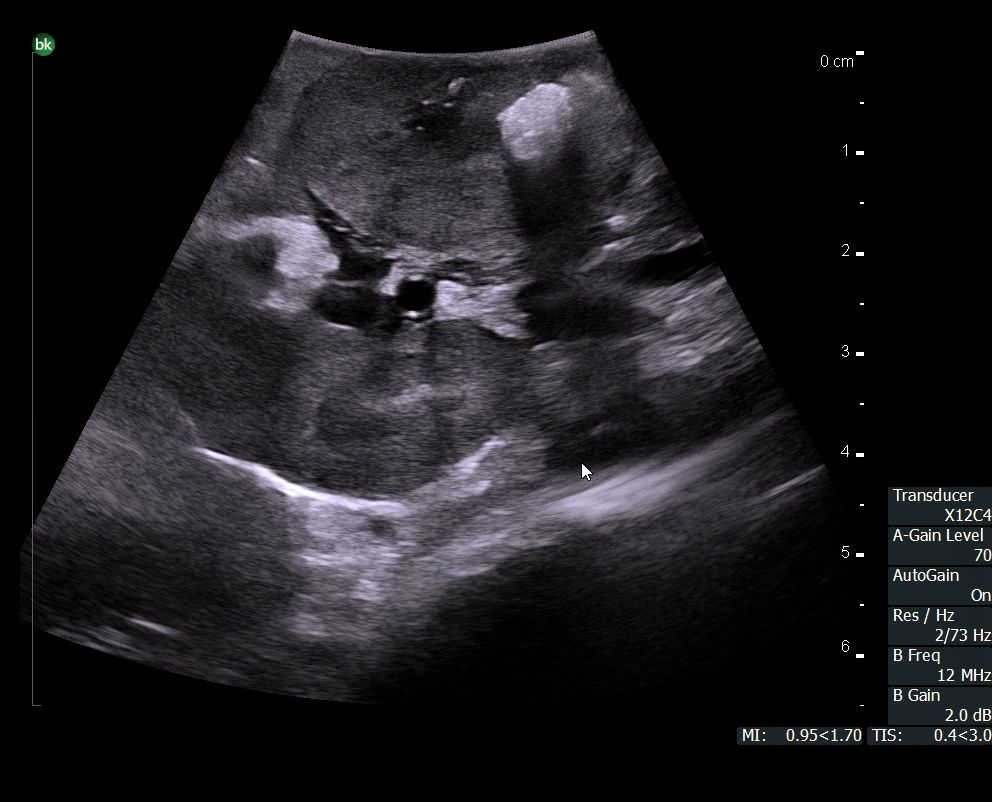

The Rob12C4 robotic transducer is designed to enhance robotic-assisted partial nephrectomy (RAPN) procedures. Intraoperative ultrasound helps surgeons locate and visualize benign and malignant lesions, key arteries, and other anatomical structures quickly, in real-time, and with precision.